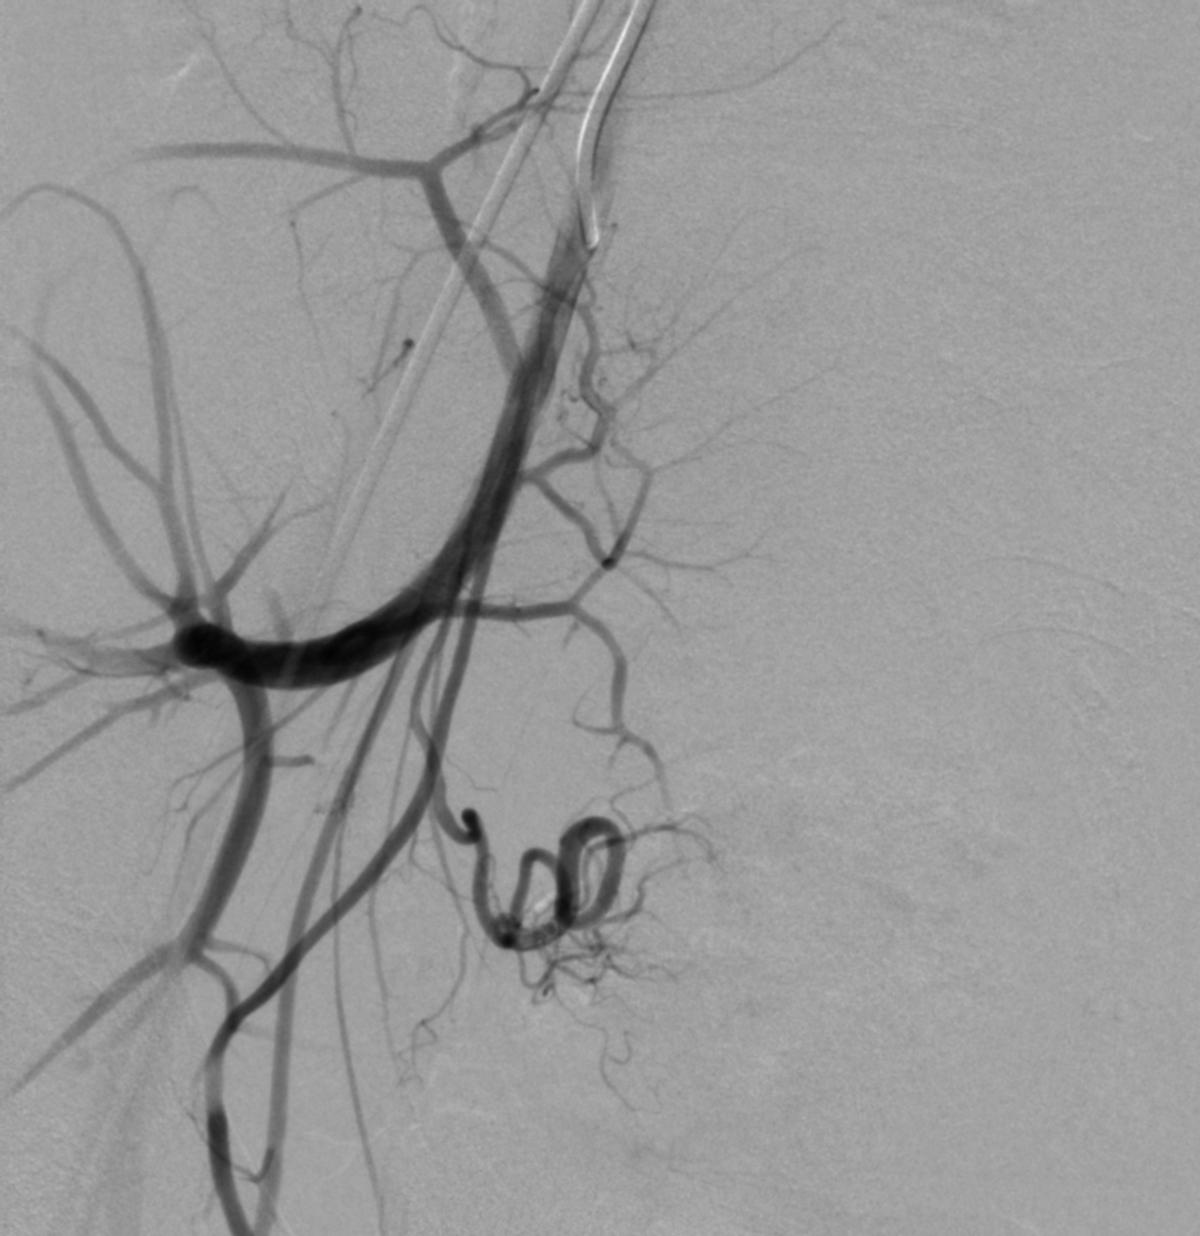

患儿完成入院前术前检查,并进行了全科的术前讨论。结合患儿体征及相关的术前检查,目*考前**虑PROS综合症。目前主要解决的是月经出血的问题,可以通过栓塞双侧子宫动脉来进行治疗。患儿全麻后,使用5F穿刺针行右股动脉穿刺,成功后置入5F血管鞘,导丝引导下置入5F Headhunter Angiopointer造影导管,在导丝引导下选入髂内动脉,进入子宫动脉,造影见左侧子宫动脉远端纤细,右侧子宫动脉螺旋增粗,微导丝引入微导管进入子宫动脉,使用聚乙烯醇颗粒栓塞剂350um-560um,栓塞微粒球(300-500um)分别行双侧子宫动脉栓塞,栓塞后造影未见子宫动脉远端分支显影。

栓塞治疗

微导管栓塞治疗